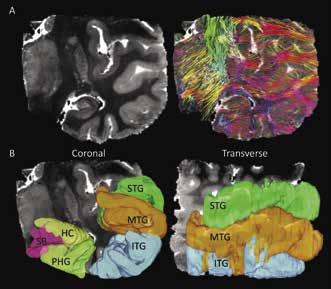

3. Results 3.1 Anatomical verses diffusion images

Figure 1 shows three anatomical views of the acquired image from the temporal lobe. The MD images are shown in the left-hand column and highlight a differentiation between white and grey matter, with grey matter regions delineated by a lighter grey color. The right column shows the corresponding diffusion encoded color (DEC) images. These images show a similar delineation between white and grey matter, possibly indicating a discrepancy in diffusion anisotropy between the two tissue subtypes. It is of note the central area of the lobe is shown as mostly blue or green, representing uniform diffusion direction. On the other hand, the cortex and hippocampus regions are multicolored, suggesting isotropic diffusion behavior occurred within the grey matter regions.

Figure 1: The left column shows a coronal, sagittal, and transverse view of the temporal lobe considered in this study. In these images the light grey regions represent areas of higher average diffusion and likely represent grey matter structures such as the hippocampus and cortex. The right column shows the diffusion encoded color images that correspond to the same slices shown in the MD images. Colors in these images group neurons with the same directional orientation.

Figure 2A shows a coronal slice of the MD image compared to the same image overlaid with all reconstructed streamlines within it. When comparing the streamlines shown in Figure 2A and the ROIs in Figure 2B, it can be determined that streamlines seem to be less dense in grey matter regions than in white matter regions. Additionally, it is shown that white matter regions appear to be mostly arranged in in the medial/lateral orientation. In Figure 3B at the tail, or fimbria, of the posterior HC, axonal projections join the selenium of the corpus callosum (scc) and a telencephalic white matter tract, the cingulum bundle (cgb). This result verifies the previously known connection of the HC to the cgb and supports the fact that DTI can accurately contribute to the discovery of grey matter interconnectivity within the TL [3].

Figure 2: (A) Coronal view of one of the TL MD maps compared to the same image showing all generated streamlines from reconstruction by computational detection and tracing of the FA vector in each voxel in the image. Streamline colors represent its 3D direction in space, with red=lateral/ medial, green=superior/inferior, and blue=anterior/posterior. Intermediate colors represent a combination of two directions. (B) Coronal and transverse views showing the three-dimensional region of interest maps drawn on the DTI image. Here the superior, medial, and inferior temporal gyri are shown (labeled as STG, MTG, and ITG), as well as the parahippocampal gyrus (PHG), subiculum (SB), and hippocampus (HC).